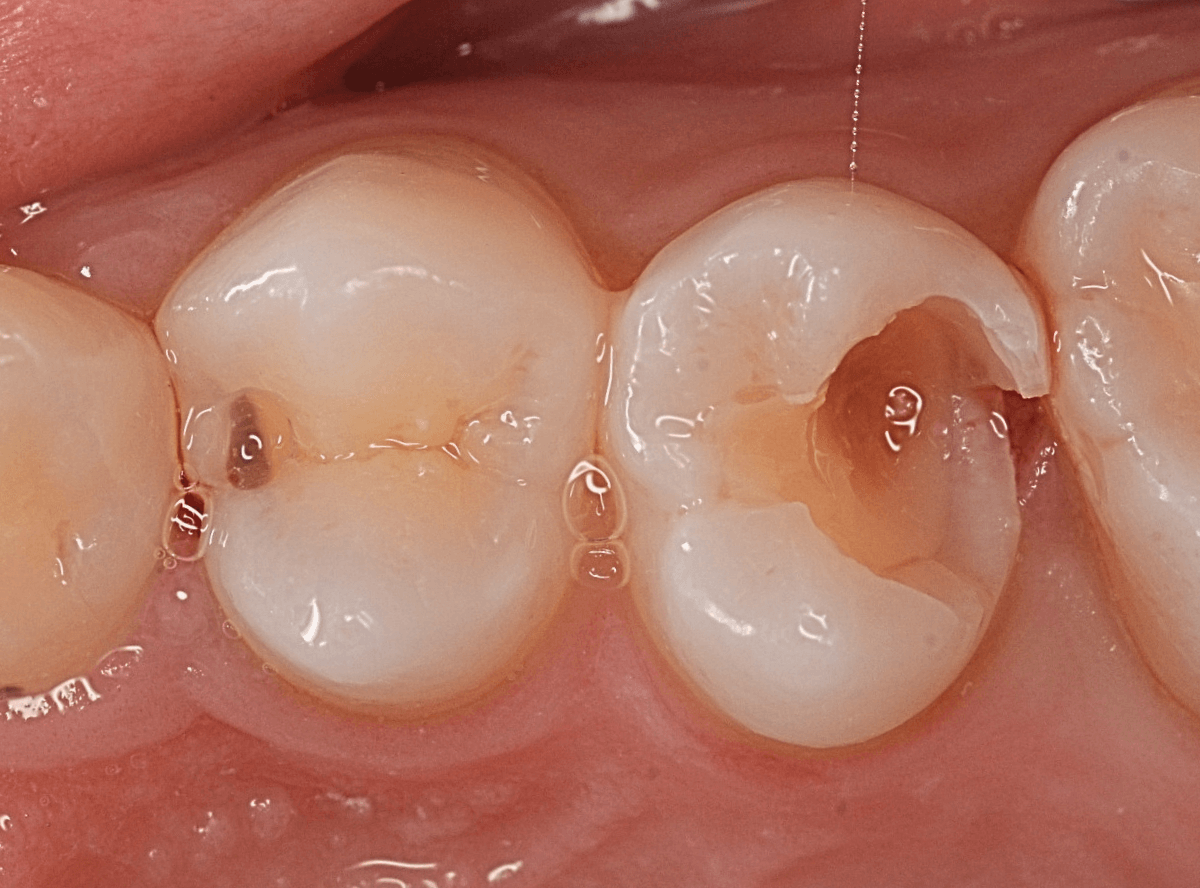

虫歯の治療希望で来院された患者さんです。

レジンが欠けて大きな穴が空いているのが見えます。

このような場合は、中で虫歯が進行している事が多いです。

(レジンの中で虫歯が進行してレジンに穴が空いた、レジンが欠けたのを放置して虫歯が進行したパターンなどがあります)